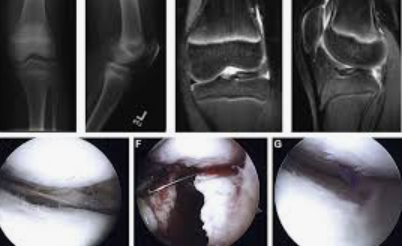

3. 메니스커스 손상

정의: 무릎의 월 모양의 연골인 메니스커스의 손상입니다.

발생 원인: 급격한 회전 운동, 무릎에 직접적인 충격, 오래된 부상 등에 의해 발생합니다.

예방 및 관리: 올바른 운동 기법, 무릎 보호대 사용 등으로 예방할 수 있습니다.

(1) 아트로스코피

최소 침습 수술로, 작은 카메라를 이용해 관절 내부를 검사하며, 동시에 문제를 해결합니다. 연골의 손상된 부분을 제거하거나 근육 및 인대의 문제를 해결하는 데 사용됩니다.

(3) 메니스커스 수술

손상된 메니스커스를 제거하거나 복원하는 수술로, 아트로스코피를 이용하여 진행됩니다. 수술 후에도 무릎 부담을 줄이기 위한 생활 습관과 꾸준한 재활 운동이 필요합니다.